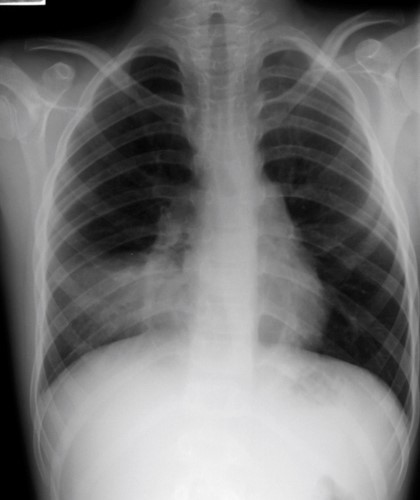

45yo non-smoker presents with rhinorrhea and sneezing

View: PA

DX: carcinoid tumor